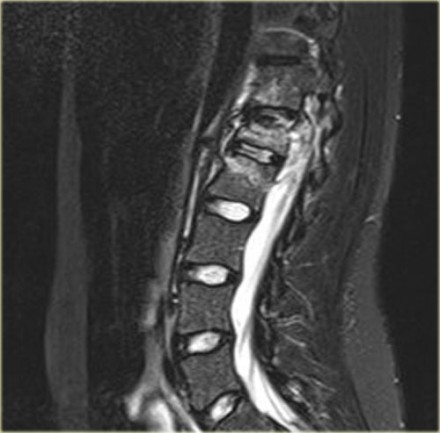

Continue with the MRI-images.

Again look at the first MR-images and decide what is going on.

Then scroll to the next images.

The findings are:

- Anterior displacement of C7 to Th1.

- Protrusion of the disc.

- Compression of the spinal cord.

- Bone marrow edema in several vertebral bodies, either due to contusion or fracture.

- Interspinous edema and disruption of the ligamenta flava C7-Th1 and supraspinous ligament Th1-Th2.

In some cases it can be difficult to decide whether there is a translation or distraction injury and we have to assume that the traumtic mechanism is a combination of forces.